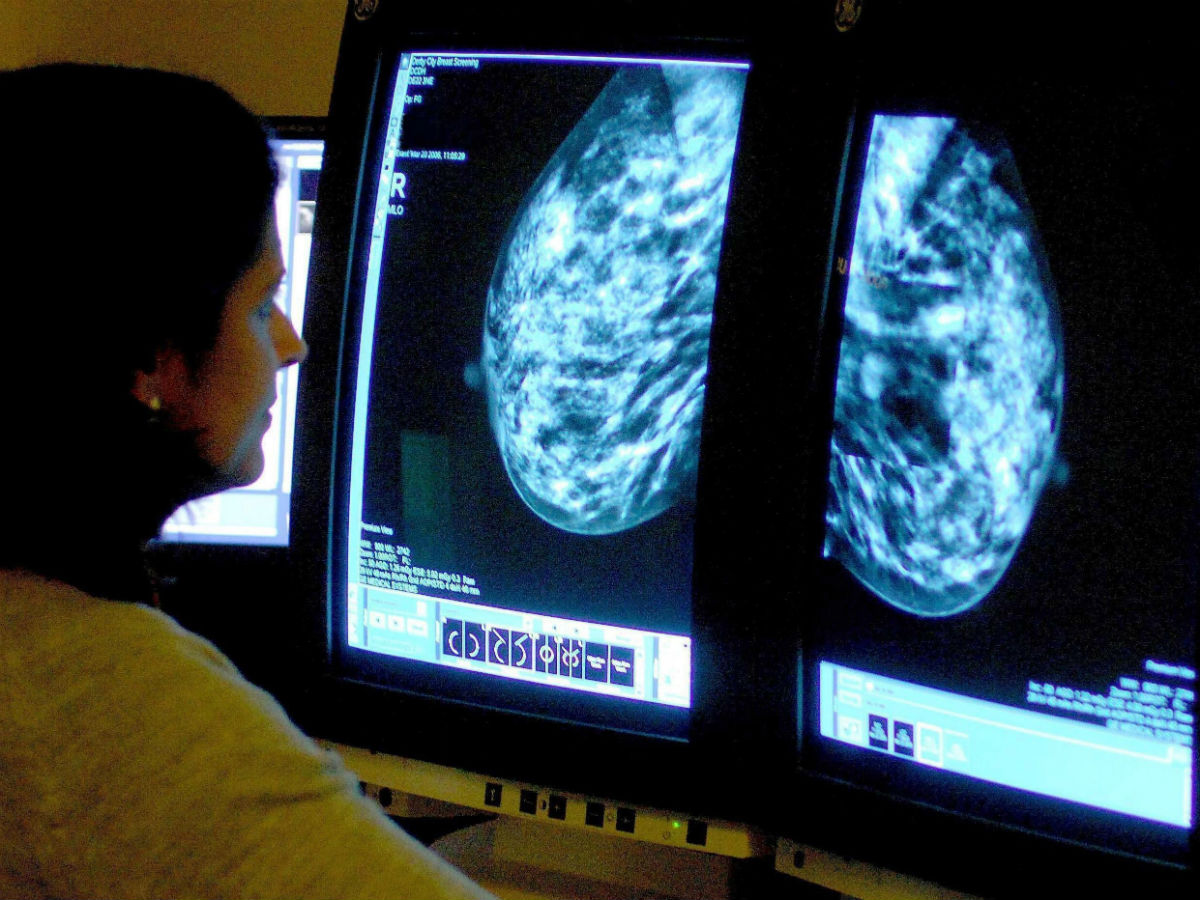

Ранее врачи самый распространенный вид рака. Как выяснилось, это рак мочеполовой системы. Причем показатель общий как для мужчин, так и женщин. На втором месте, если говорить о заболеваниях только прекрасной половины человечества, – рак молочной железы.